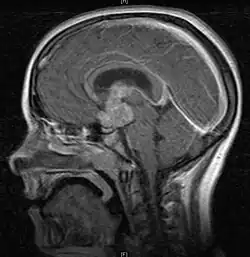

• Mainly located in midline structures, suprasellar region or pineal gland, also basal ganglia and hypothalamus

• Bifocal germinomas (synchronous suprasellar and pineal tumors) regarded as M+ in USA but M0 in Europe

• Natural spread believed to be along subependymal lining of 3rd and 4th ventricles, leading to intraventricular relapse before spinal dissemination

Location